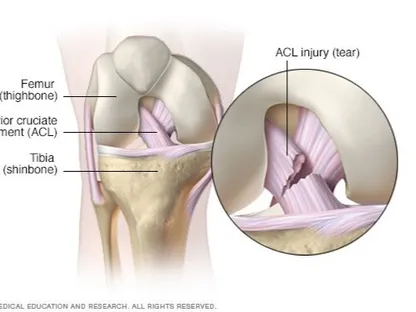

- الركبة

من خلال تدويرها حول محورها أثناء ممارسة نشاط رياضي.